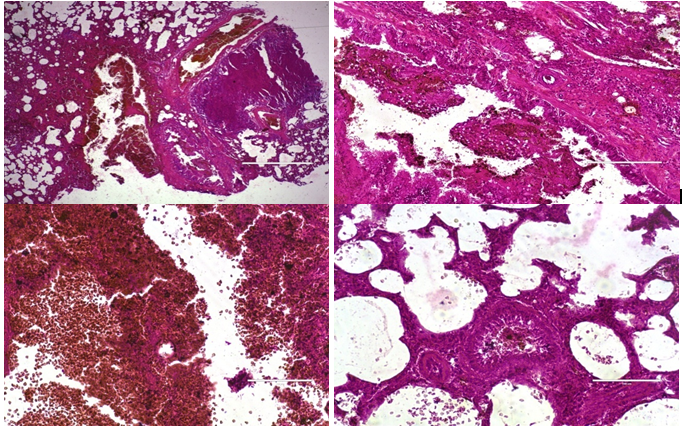

It was found that in the group receiving a dose of staphylococci in the amount of 3 million units, there was a more pronounced development of the pathological process compared to the group of animals administered a dose of 2 million units of staphylococci (Figure 1) (Figure 2). These changes were more significant on the 7th day of the experiment.

Figure 2 Cloth of a light rat on the 7th day of infection with staphylococci in a dose of 3 million units. Purulent plugs in the lumens of bronchioles, foci of destruction of lung tissue, focal acute emphysema. Uvel. 10х10, 10х20, Color: hematoxylin-eosin.

Among acute inflammatory cells to the 13-th day increased number of mononuclear cells. Decreased tissue destructive processes in the lung parenchyma, but also circulatory disorders accompanied by hyperemia and focal inflammatory diapedetic hemorrhages, uneven alveolar edema. Along with these changes, there was also a decrease in the manifestations of reactive hyperplasia of peribronchial lymphoid tissue, which may be a consequence of depletion of lymphoid tissue in response to the inflammatory process (Figure 3) (Figure 4). Thus, morphofunctional changes in the dynamics of observation indicate the development of inflammatory phenomena in the lung tissue, depending on the dose of the infection.